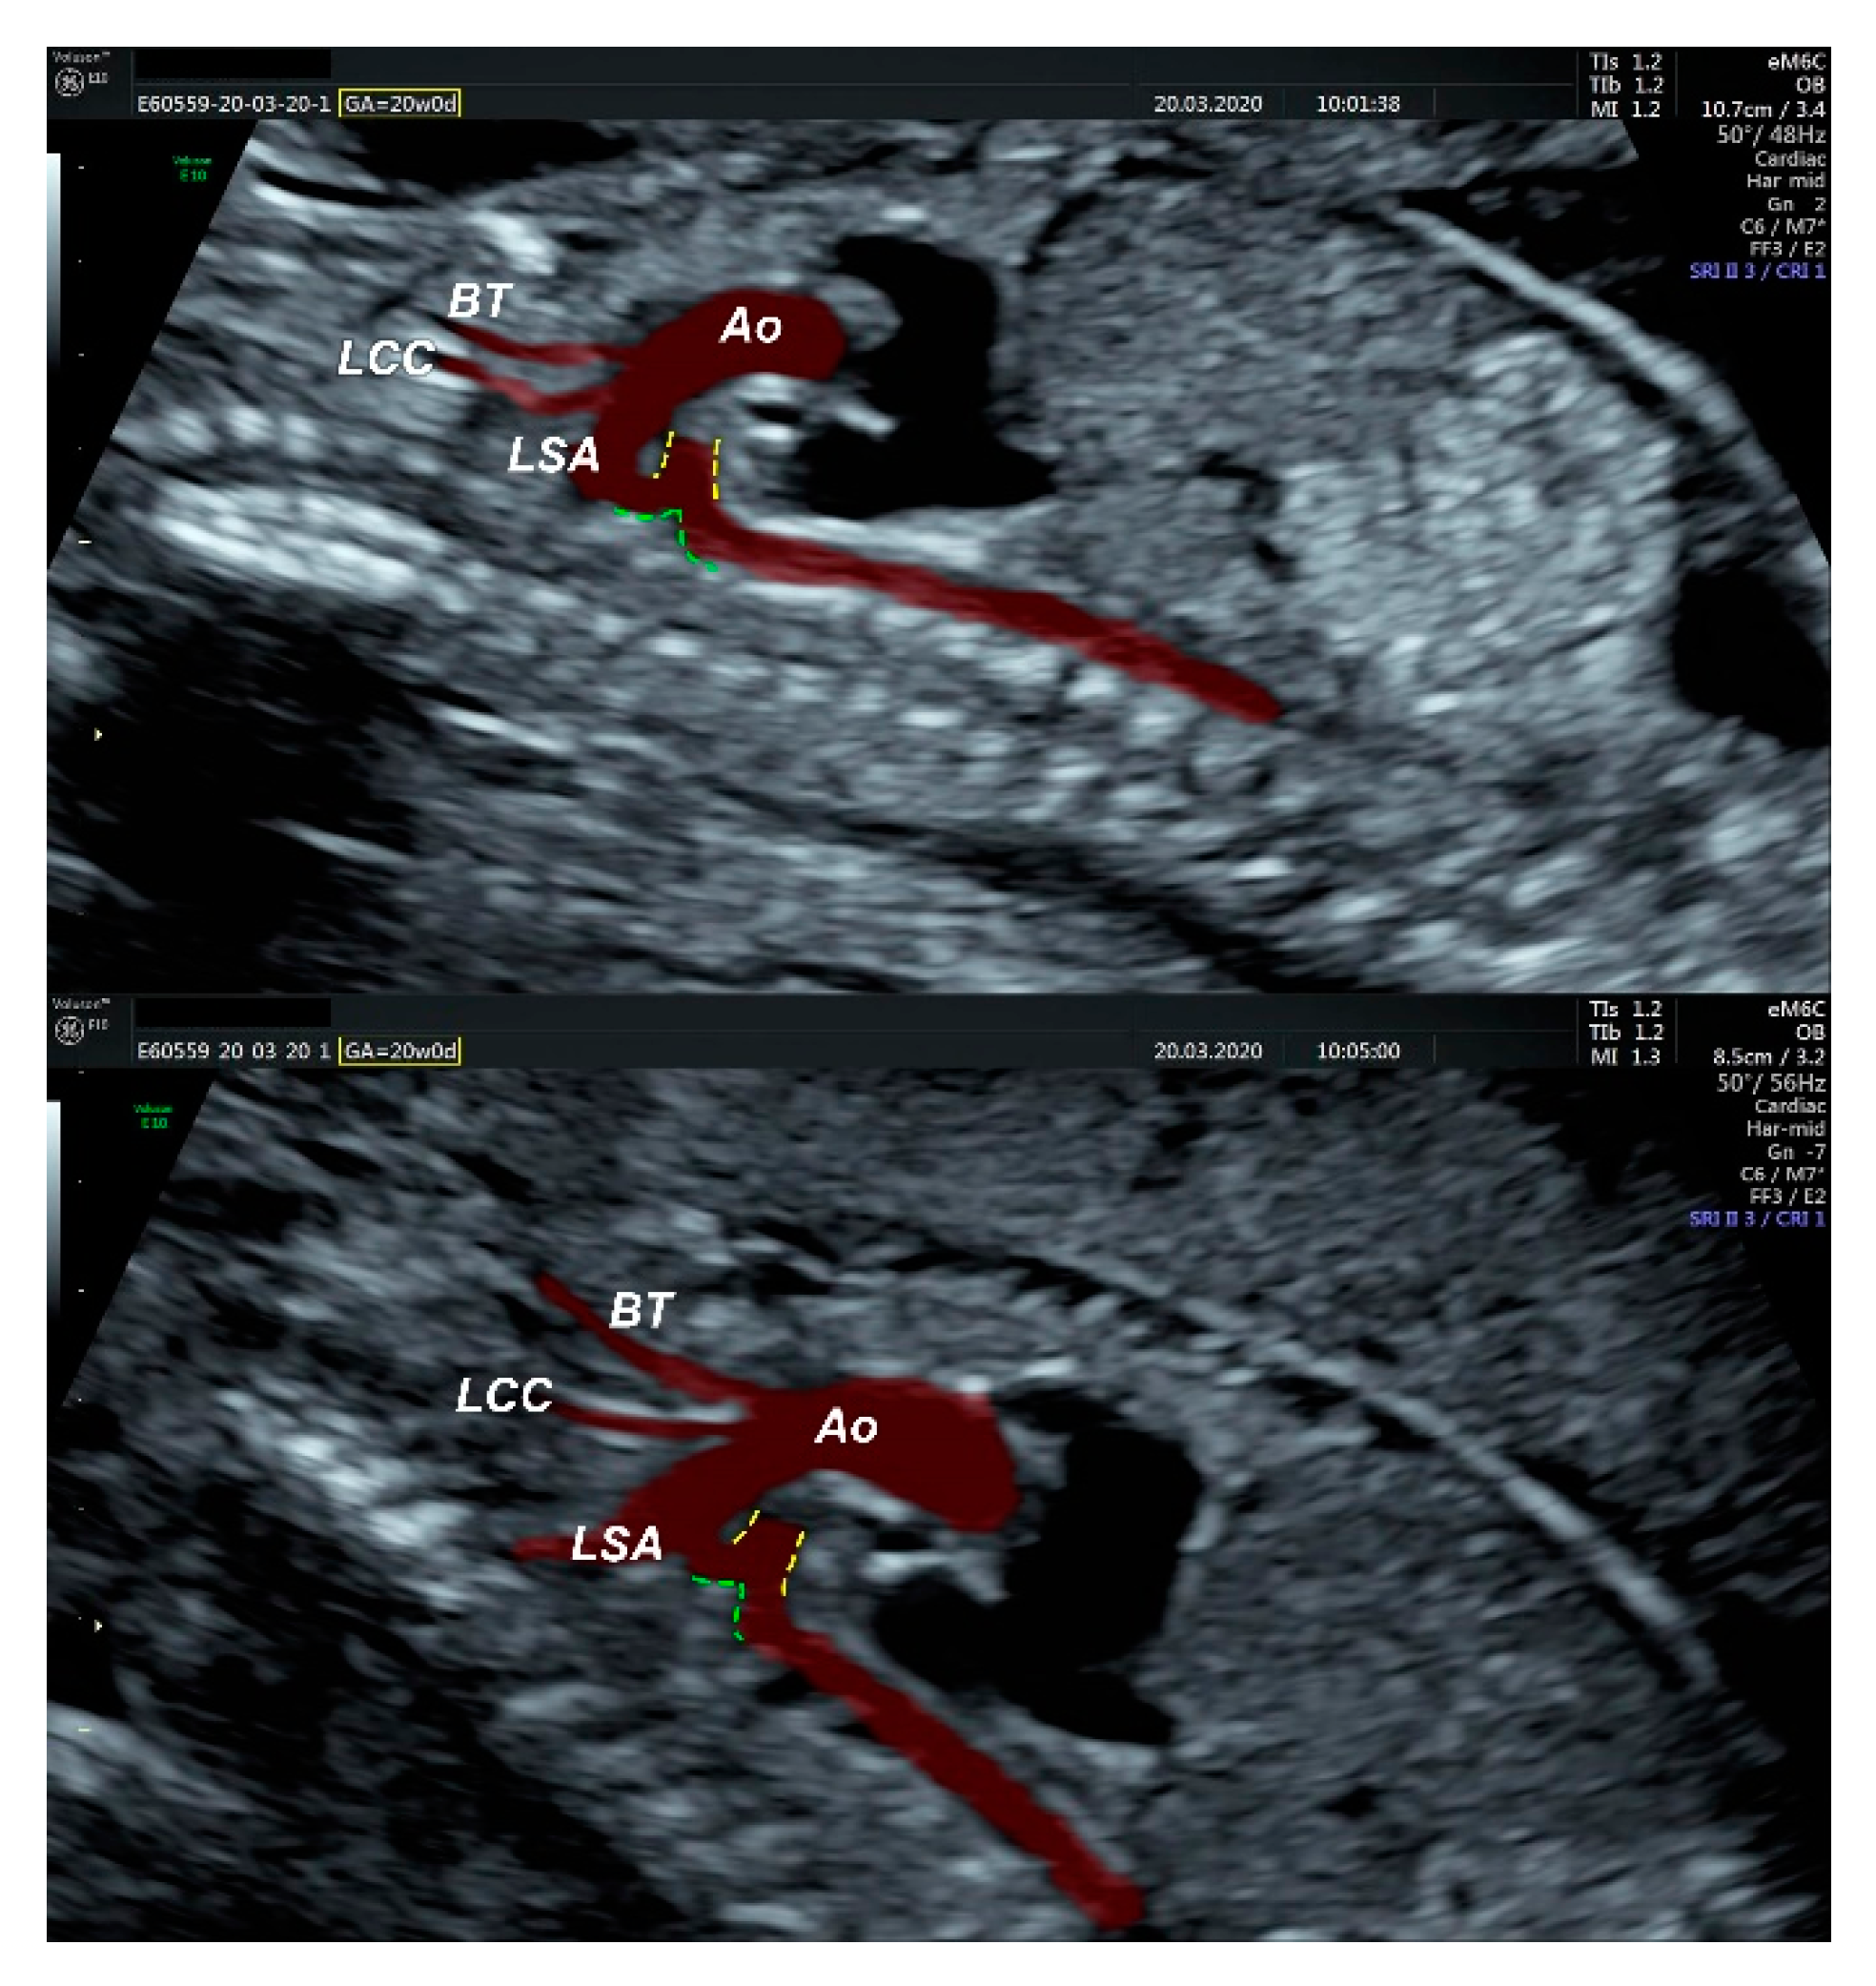

- an isolated aortic arch anomaly (supposedly aneurysmal dilation from which the left common carotid artery emerges) and coarctation of the aorta with the anterograde flow;

- ventricular septal defect, coarctation of the aorta, and a vascular formation located superior from the aortic arch with the appearance of an arteriovenous fistula;

- aneurysmal dilation located above the pulmonary trunk bifurcation and a dilated left common carotid artery with a retrograde flow;